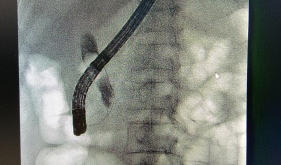

茂名市人民医院内镜中心承继既往优势、融合多学科特长,是一一个围绕消化系统腔道进行检查、诊断、治疗的科室,面积约700平米,每年接诊约4万例内镜诊疗,拥有一流的消化内镜专家团队,目前有主任医师3名,副主任医师2名,主治医师3名,副主任护师2名,主管护 师6名,护师4名,护士1名,技师1名,中心拥有世界一流内镜软硬件平台 ,包括高清放大胃镜、结肠镜、十二指肠镜、超声内镜、ERBE电外科工作站、胶囊内镜及先进的全自动内镜消毒清洗设...